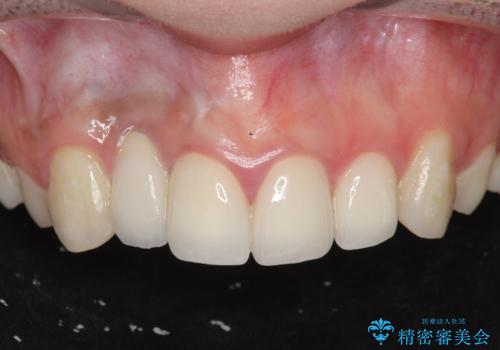

前歯の虫歯 オールセラミック治療

【オールセラミッククラウン】他院で入れた被せものがすぐとれる